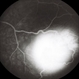

- retinal capillary hemangioblastoma, lipid exudation

- Retinal capillary hemangioblastoma with lipid surrounding.